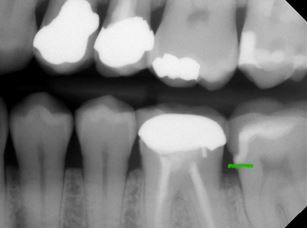

Typically, a post-op bitewing is taken to confirm the proper adaptation of restorative material to tooth structure, mainly when deep margin elevation is used to elevate a margin for indirect restorations. Deep margin elevation can be utilized near the bone with negligible effects on the biologic width when performed in a limited area.

In some cases, the matrix band may need to be adapted to accommodate the prep’s subgingival aspect. A #2 Tofflemire band or a modified #1 Tofflemire band can extend the matrix to ensure an adequate seal of the margin elevation material to the tooth.